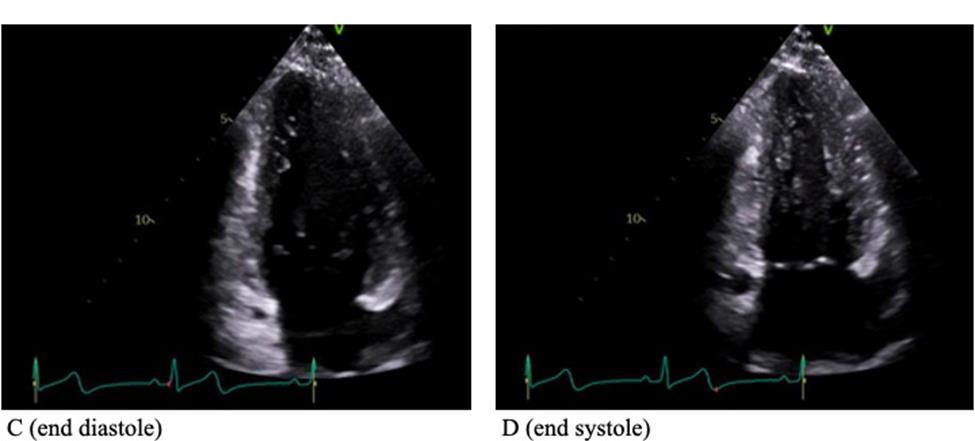

CARDIAC SARCOIDOSIS WITH PREDOMINANT RIGHT VENTRICLE INVOLVEMENT

Hannah Hart1, Devika Aggarwal1, Soumya Gupta1, Vikram Agarwal1, Isha Ranadive1

1Mount Sinai Morningside-West Hospitals, Icahn School of Medicine at Mount Sinai, New York, NY, United States

Presented at both the American College of Cardiology (ACC) Annual Meeting that was held in Atlanta, Georgia, United States from April 6-8, 2024 and the Annual Mount Sinai Health System Department of Medicine Research Day that was held in New York, New York, United States on May 6-7, 2024.